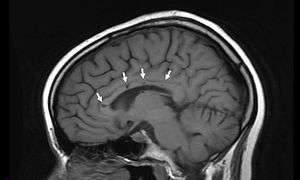

Sagittal T1 image in a 19-year-old woman with Susac's syndrome showing the pathognomonic central callosal “holes” (microinfarcts) of SS. These residual “holes” (and sometimes, “spokes”) develop as the acute callosal changes resolve.

Radiographic Appearance: In a recent analysis (Susac et al., 2003), MRI images from 27 patients fulfilling the diagnostic criteria of Susac's syndrome were reviewed. Multifocal supratentorial lesions were present in all patients. Most lesions were small (3 to 7 mm), though some were larger than 7 mm. All 27 patients had corpus callosum lesions. These all had a punched-out appearance on follow up MRI. Though most commonly involving white matter, many patients also had lesions in deep grey matter structures, as well as leptomeningeal enhancement. Multiple sclerosis (MS) and acute disseminated encephalomyelitis (ADEM) can mimic the MRI changes seen in patients with Susac's syndrome. However, the callosal lesions in Susac's syndrome are centrally located. In comparison, patients with MS and ADEM typically have lesions involving the undersurface of the corpus callosum. Deep gray matter involvement commonly occurs in ADEM but is very rare in MS. Leptomemingeal involvement is not typical of either MS or ADEM. What this means is that if you have 10 lesions in the brain of an MS patient, you may find one in the corpus callosum. If you have 10 lesions in a Susac patient, more than half will be in the corpus callosum.